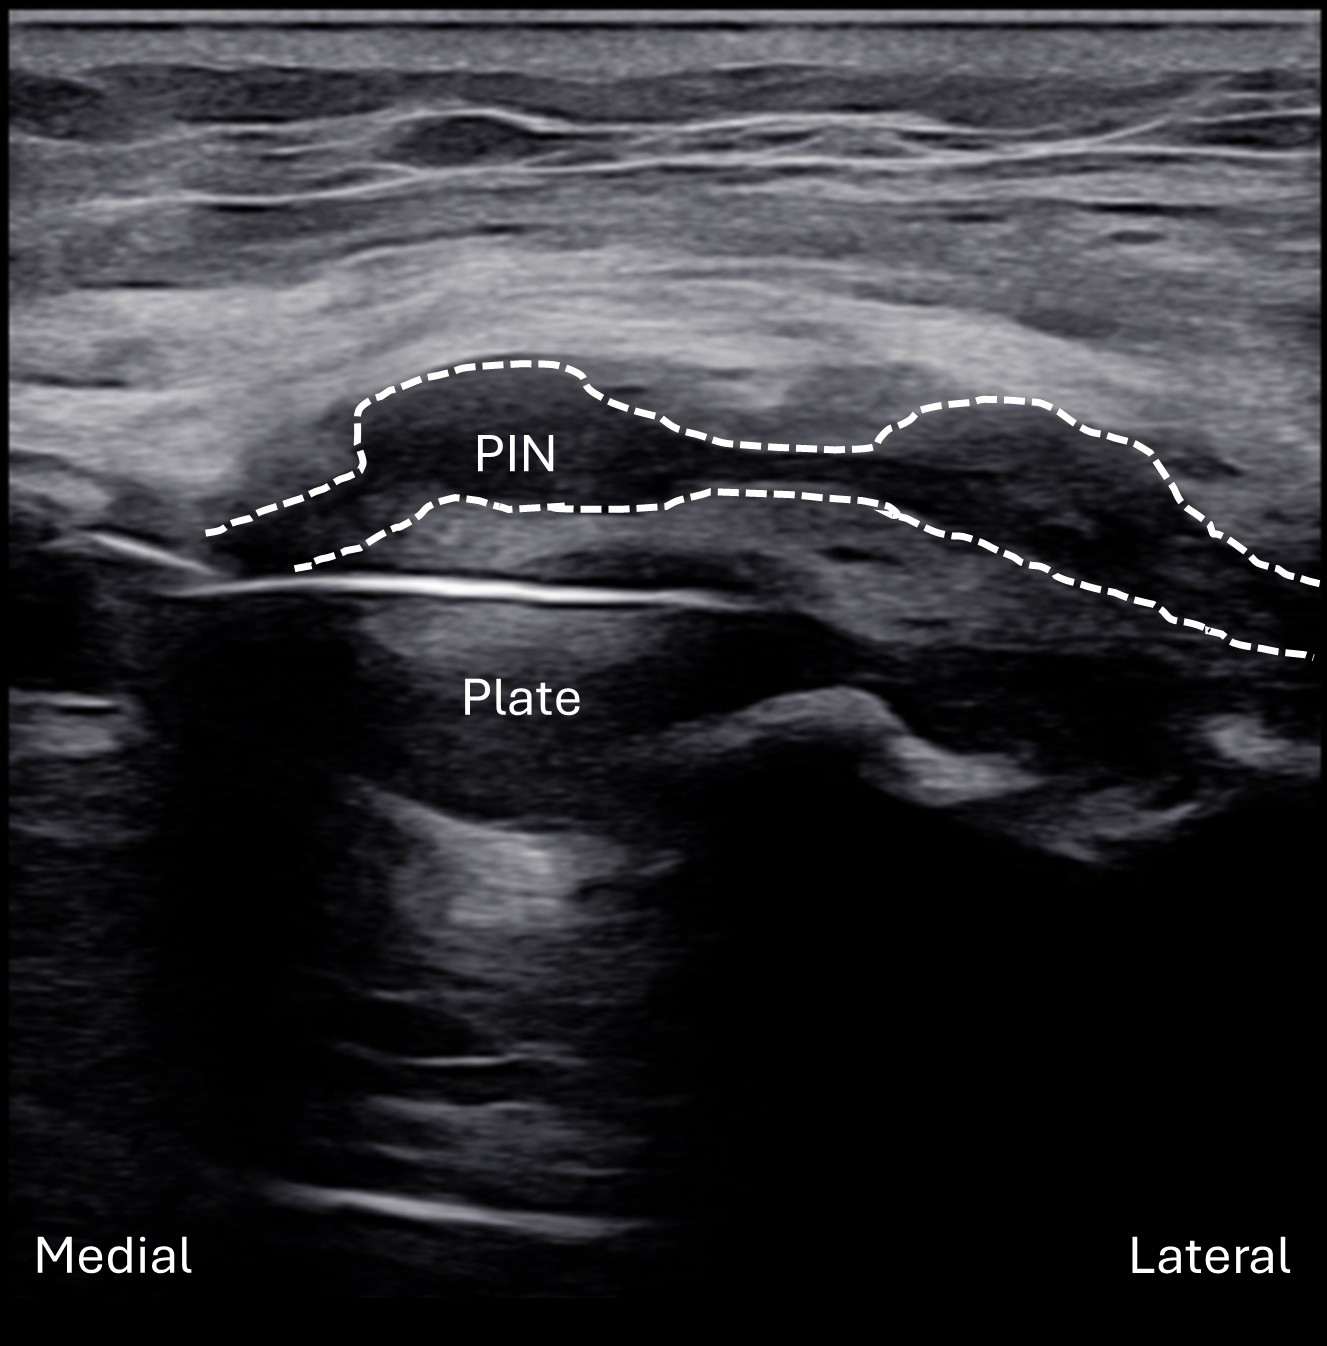

Labeled long axis view of the left PIN within the radial tunnel. There is multifocal enlargement of the PIN (dashed line) which is hypoechoic with a complete loss of normal intraneural fascicular architecture. The architecture of the nerve appears as more of a “dumbbell” shape within the tunnel. These findings may be representative of two focal neuromas-in-continuity. Deep to the nerve, the proximal radius plate can be seen from the prior ORIF. The superficial and deep heads of the supinator muscle are both markedly hyperechoic which is likely suggestive of muscle denervation.

Unlabeled long axis view of the left posterior interosseous nerve (PIN) within the radial tunnel.